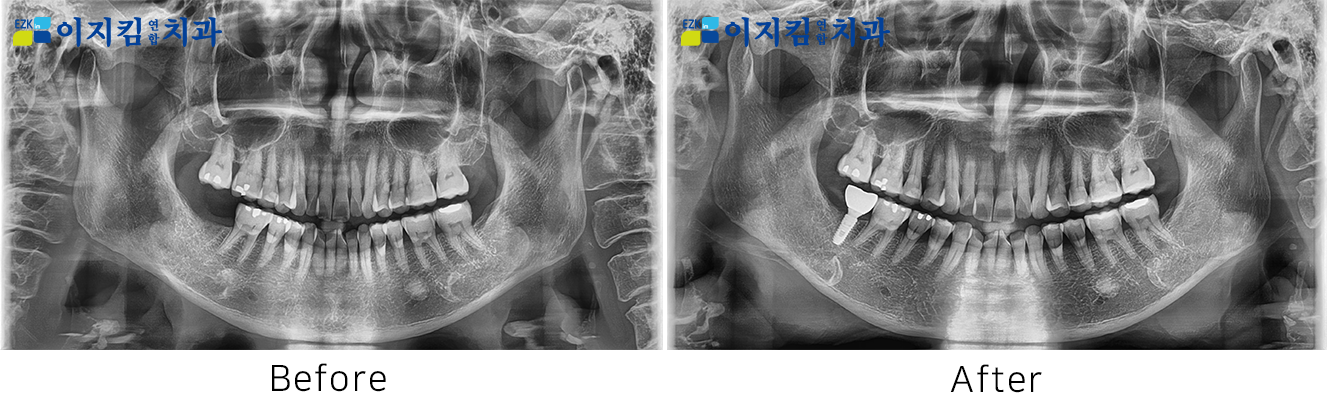

ÀÓÇöõÆ® Àü ¡¤ ÈÄ »çÁø

[

Á¶È¸¼ö : 3206

]